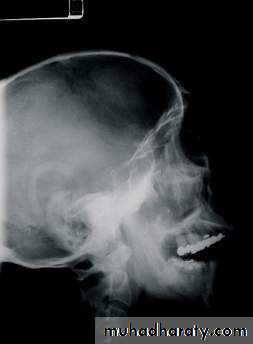

Radiographic Evaluation

• Plain Films• Lateral Skull

• Waters View

• Posteroanterior view of skull

• Submental vertex

• CT Scan

• 1.5 mm cuts

• axial and coronal views

Lateral skull

Water’s ViewCT Scan